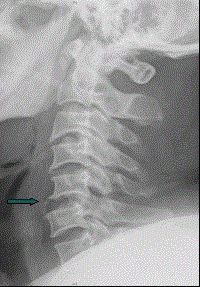

患者男,38岁,车祸伤后导致颈部疼痛、四肢瘫痪,排尿、粪失禁,ASIA分级C级,入院时间为伤后6 h,佩戴颈托入院。于急诊行颈椎正侧位X线片(如图)。...

问题 患者男,38岁,车祸伤后导致颈部疼痛、四肢瘫痪,排尿、粪失禁,ASIA分级C级,入院时间为伤后6 h,佩戴颈托入院。于急诊行颈椎正侧位X线片(如图)。 为明确诊断,需做的进一步检查和处理是(提示 入院给予MP治疗,并控制了上消化道出血。)

选项 A、SEP检查 B、头颅牵引 C、CT三维重建 D、血离子 E、MRI

答案 ABCDE

解析 ABCDE